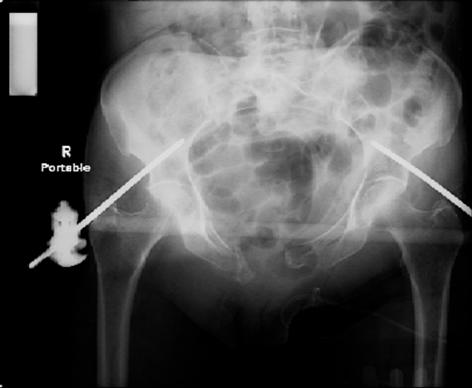

attached are images of a 70 year old female after peds versus car. her own car ran her over.

injuries are limited to the pelvis. left rami open and visible in a 10cm vertical laceration just lateral to left labia majora. wound is grossly clean. no vaginal and no urinary issues. CT scan shows widening of both SI joints anteriorly but I think this is vertically stable pattern.

pt treated that night with I/D and supra-acetabular frame to close the ring. consideration was given for SI screws bilateraly, but given time of night and other factors decision made not to proceed.

so the question is what next operatively if anything? concerns are infection, nonunion anteriorly and possible incompetence of the pelvic floor which may lead to prolapse issues. right rami are comminuted and plating may entail ilioinguinal approach to extend plate laterally to right iliac wing. retrograde screw up right rami is an option but I am not convinced it will add much. adding SI screws very doable, but major concern is restoring anterior ring. so far wound is clean and closed over a drain, and I have no plans to open it back up and wash again.